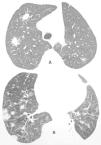

La tomografía computarizada (TC) mostraba opacidades nodulares con márgenes mal definidos en ambos pulmones, pero sobre todo en el derecho y una atelectasia en el lóbulo inferior izquierdo con bronquiectasia (fig. 1). Las pruebas de laboratorio fueron normales. La broncoscopia con fibra óptica mostró estenosis en la luz del lóbulo inferior izquierdo, sin lesión de la mucosa. El lavado broncoalveolar dio negativo para células neoplásicas, hongos y micobacterias. El cepillado y la biopsia bronquial dieron resultados negativos respecto a neoplasia maligna. La biopsia a pulmón abierto reveló proliferación de células plasmáticas bien diferenciadas. La inmunohistoquímica mostró células tumorales que dieron positivas para cadenas ligeras tipo kappa. No se detectó ninguna proteína Jones-Bence en la orina. Un examen óseo y una biopsia de médula ósea aportaron resultados negativos para mielomatosis. La paciente recibió quimioterapia, y tres años después del diagnóstico se encuentra bien y sin síntomas.